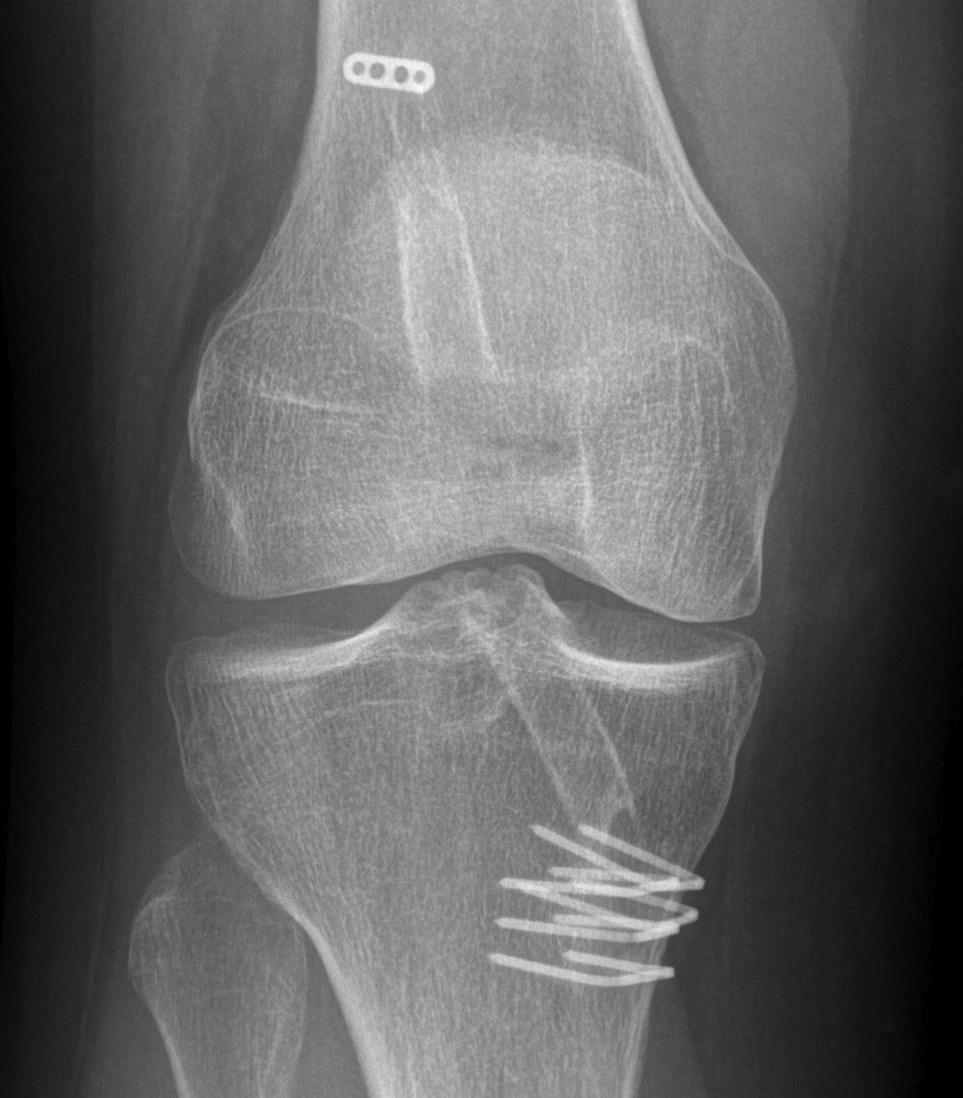

E. Tunnel Lysis

Very common, cause unknown

No evidence that contributes to instability

Important in revision setting

Cause

- more common tibial side than femur

- tends to stop after 3/12

- postulated to be from synovial fluid pistoning

- hence fluid finds it easier to come down tibial tunnel as screw placed outside in

- also seen more on femoral side with endobutton (windscreen wiper effect)